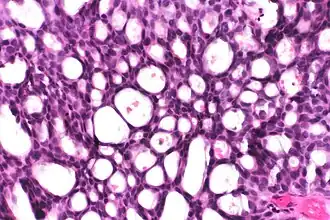

Cribriform: Solid with multiple clear spaces.

Cribriform: Solid with multiple clear spaces. -